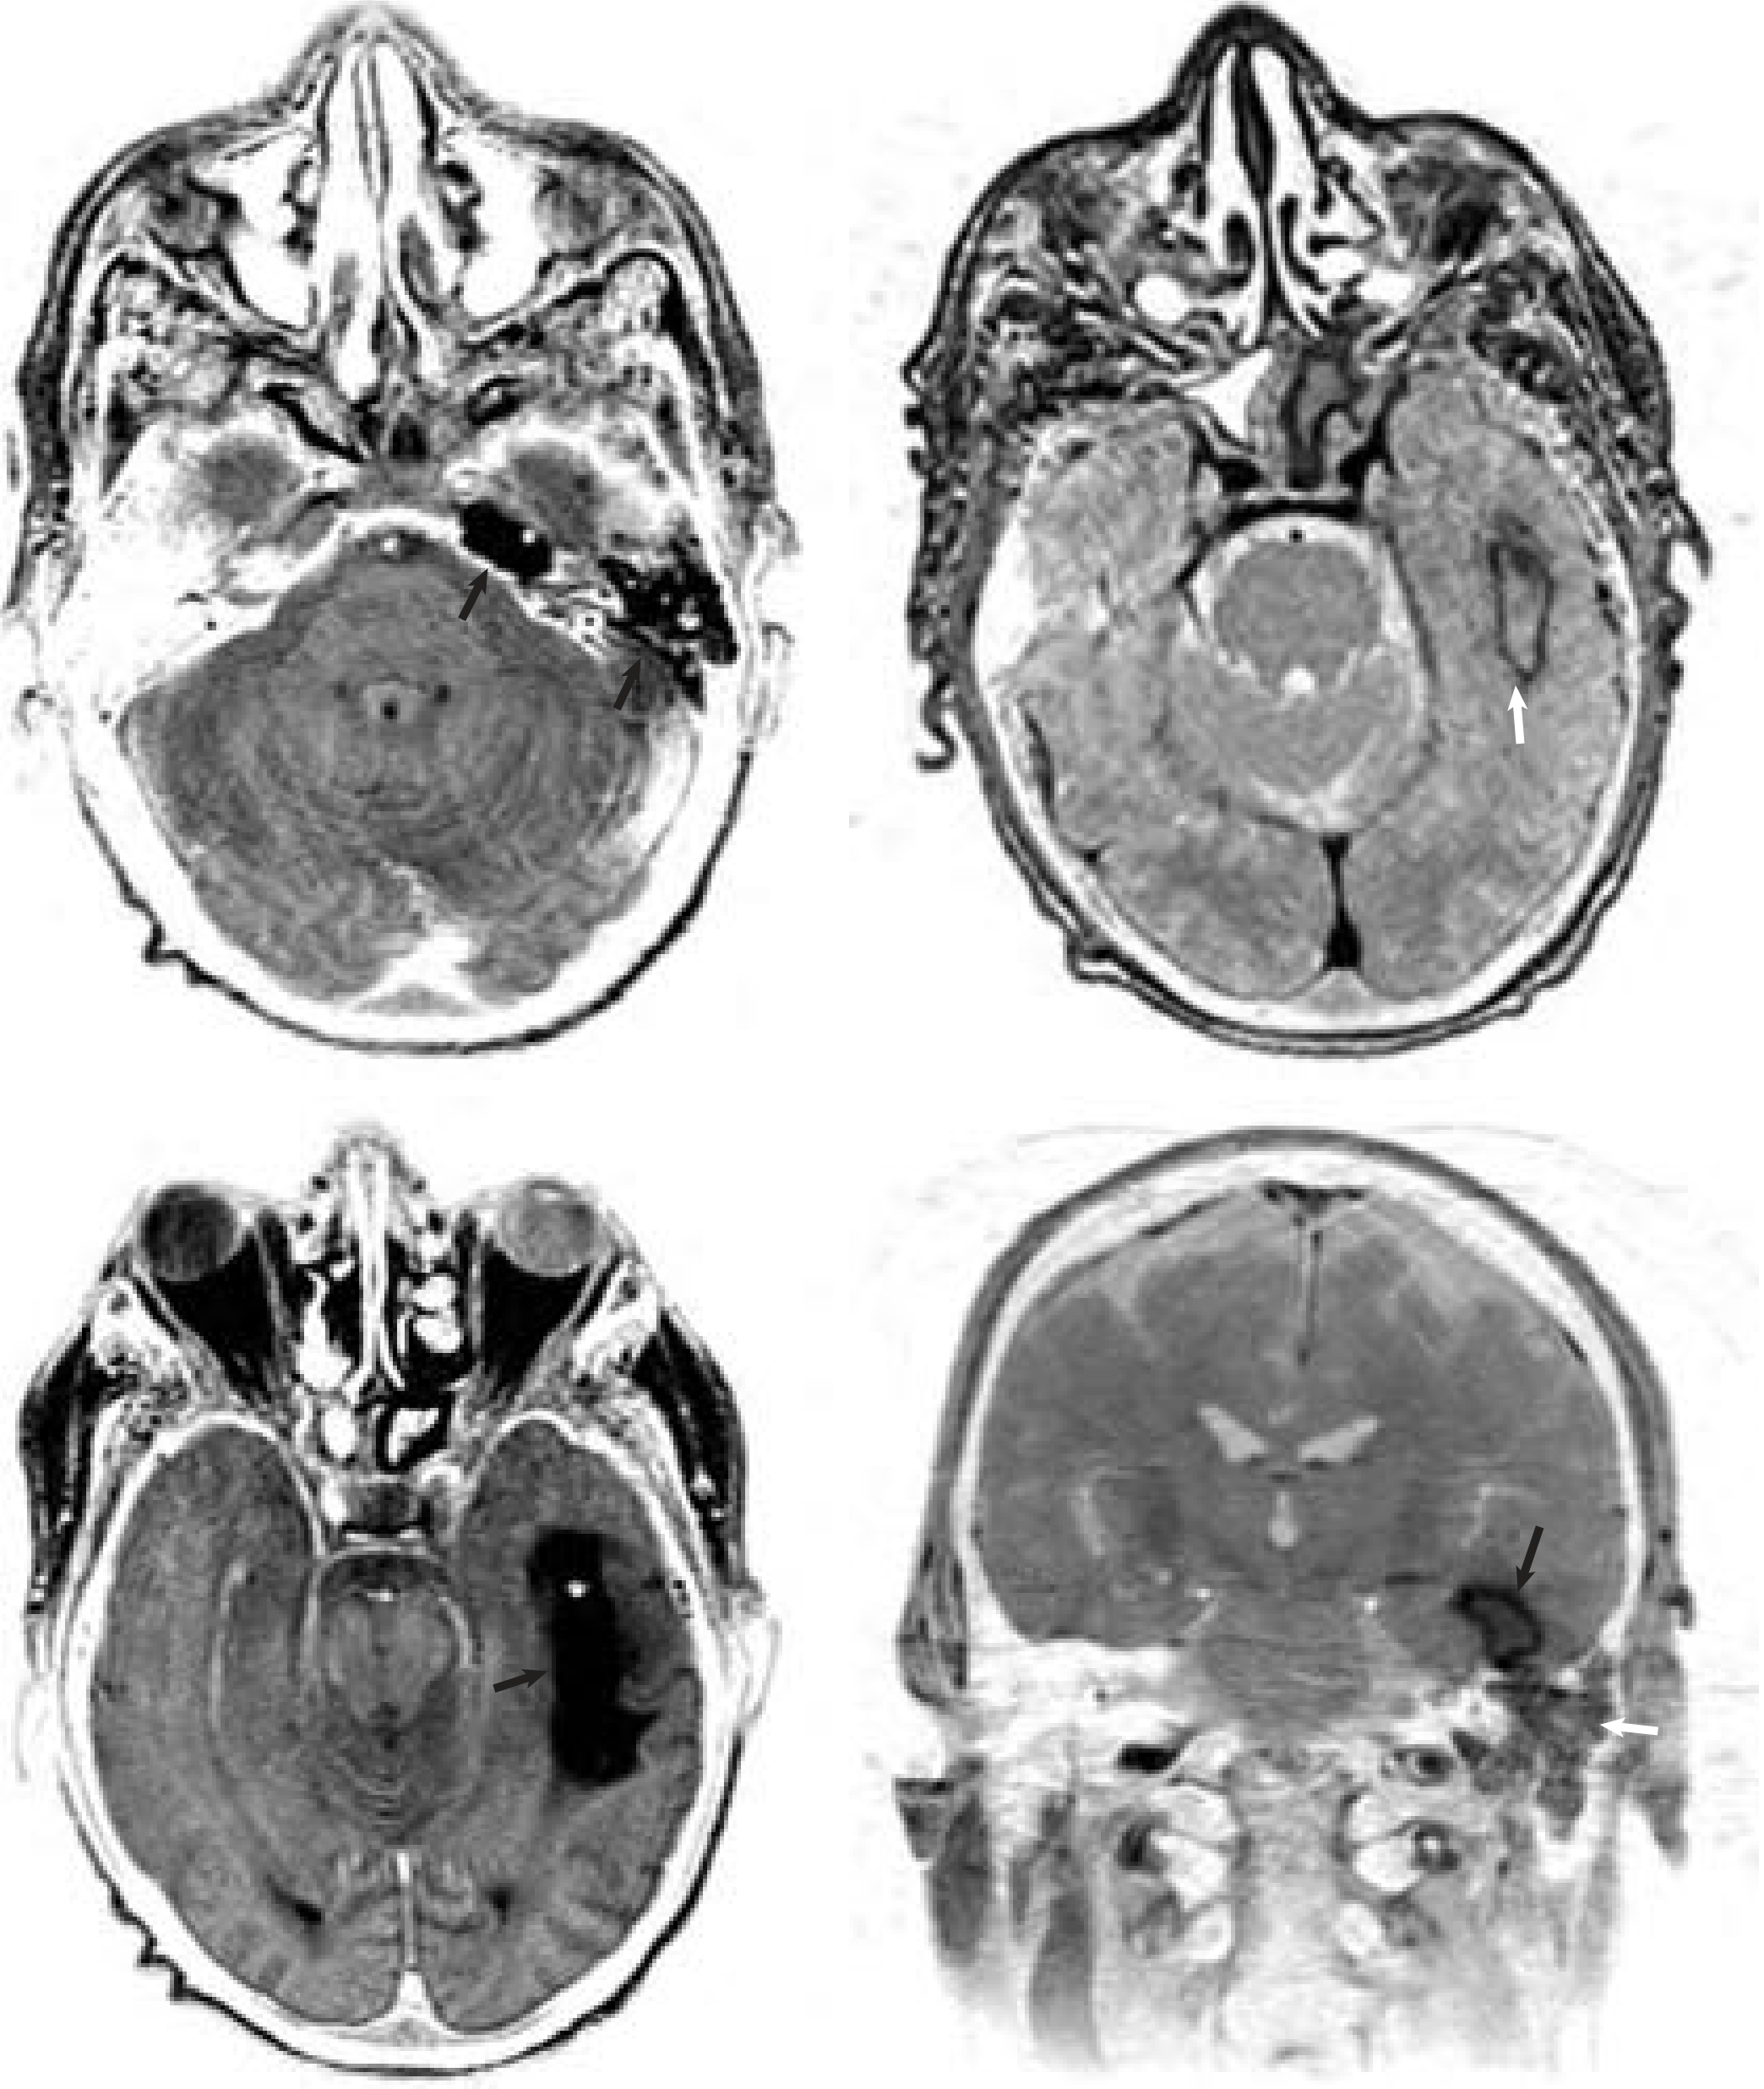

Sigmoid sinus thrombosis on CT

CT: absent enhancement of left sigmoid sinus with opacified mastoid (white arrow); absent flow in left internal jugular vein (black arrow).

MRV showing sigmoid-transverse sinus occlusion

MR venogram: occlusion of left transverse-sigmoid sinus system.